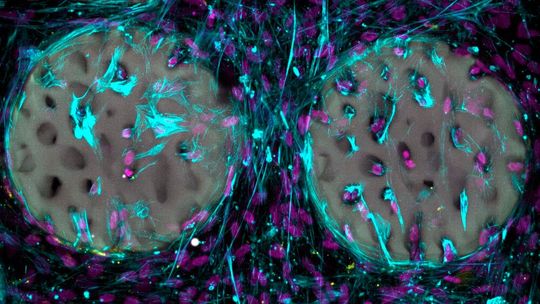

Ein gutes Zeichen: Knochenbildende Zellen (hellblau) mit Zellkernen (violett) haben ein Hydrogel, das wie Knochen strukturiert wurde, bereits besiedelt.

(Bild: Margherita Bernero / ETH Zürich)

Bisher haben die Forscher das Material erst im Reagenzglas getestet. Dabei zeigte sich, dass knochenbildende Zellen das strukturierte Hydrogel rasch besiedeln und beginnen, Kollagen zu bilden, ein wichtiger Bestandteil des Knochens. Die Tests zeigten weiter, dass das Material biokompatibel ist und die knochenbildenden Zellen nicht schädigt. Die Forscher haben das Basismaterial patentieren lassen und möchten es der medizinischen Industrie zugänglich machen.